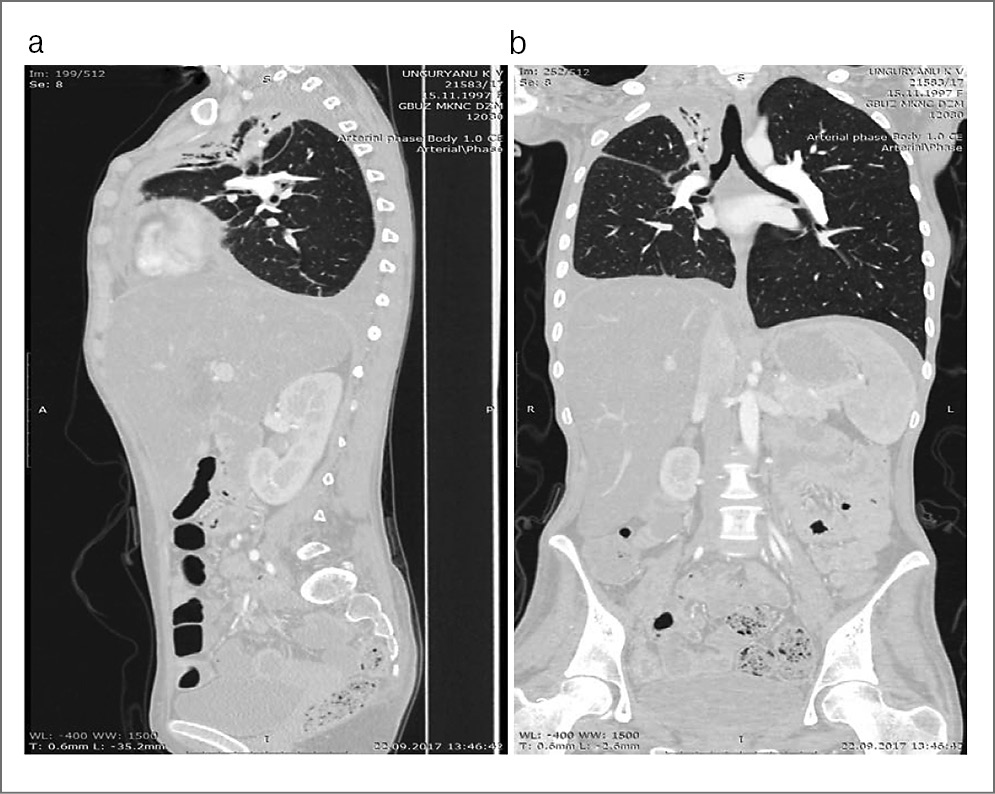

По данным КТ грудной клетки и органов брюшной полости с контрастным усилением выявлены следующие изменения – ателектаз верхней доли правого легкого. В ателектатически измененной легочной ткани имеются единичные кальцинаты. Просвет сегментарных бронхов заполнен содержимым, прослеживаются не на всем протяжении. Единичные мелкие очаги (до 3–4 мм) в левом легком. Выпот в плевральной полости справа (рис. 3, а, b).

Рис. 3 (а, b). КТ-энтерография органов брюшной полости, органов грудной клетки с внутривенным контрастированием от 22.09.2017.